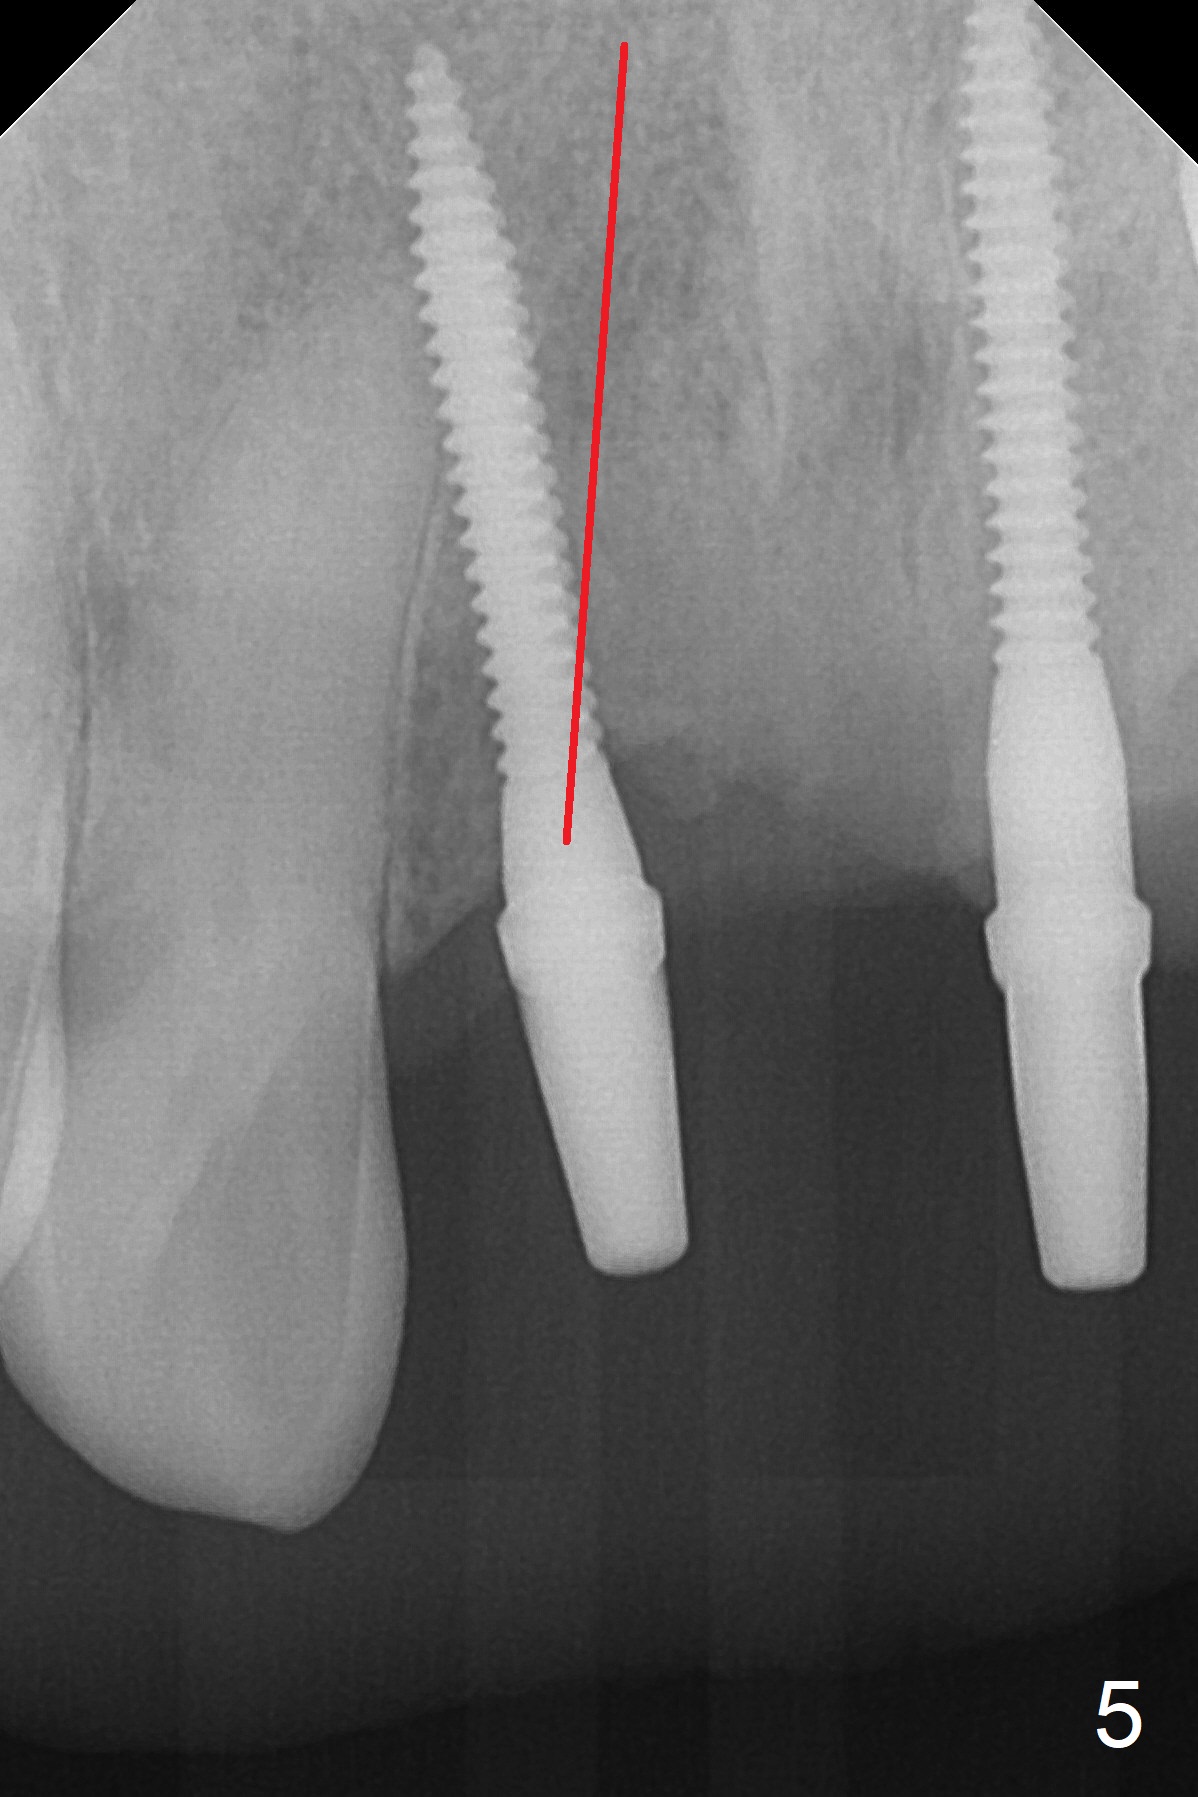

For implant placement of the atrophic ridge (Fig.1), osteotomy starts at #8 and 9 (Fig.2). Change in trajectory at #8 seems acceptable (Fig.3 (arrowheads: upper midline suture)). But it relapses when a 2x14(2) mm implant is placed (Fig.4 (2x14(4) mm at #9)). It appears that a drastic change in trajectory is necessary (Fig.5). In fact it is difficult to change the trajectory with the flexible 1.2 mm drill. Lindamann bur can be used for this purpose initially (coronally). The osteotomy should be moved mesially prior to reuse of the 1.2 mm drill for depth.